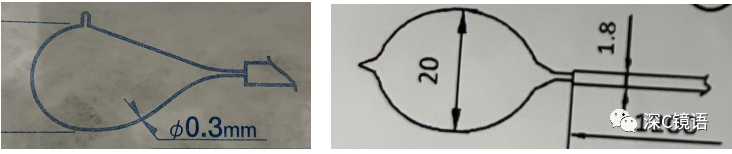

医疗方面:目前,我科室能开展呼吸内镜相关诊断与治疗技术,具体如下:诊断技术包括经支气管镜冲洗术、灌洗术、刷检术、活检术、针吸活检术、环形超声以及内科胸腔镜等;治疗技术包括球囊扩张术、支架植入术、高频电凝术、高频电圈套治疗、激光治疗、冷冻治疗、局部注药治疗等。秉承“患者所需,医者所为”的宗旨,为肺部感染、肿瘤、气道异物、不明原因胸腔积液,尤其是气道结核的患者,提供综合诊治方案。